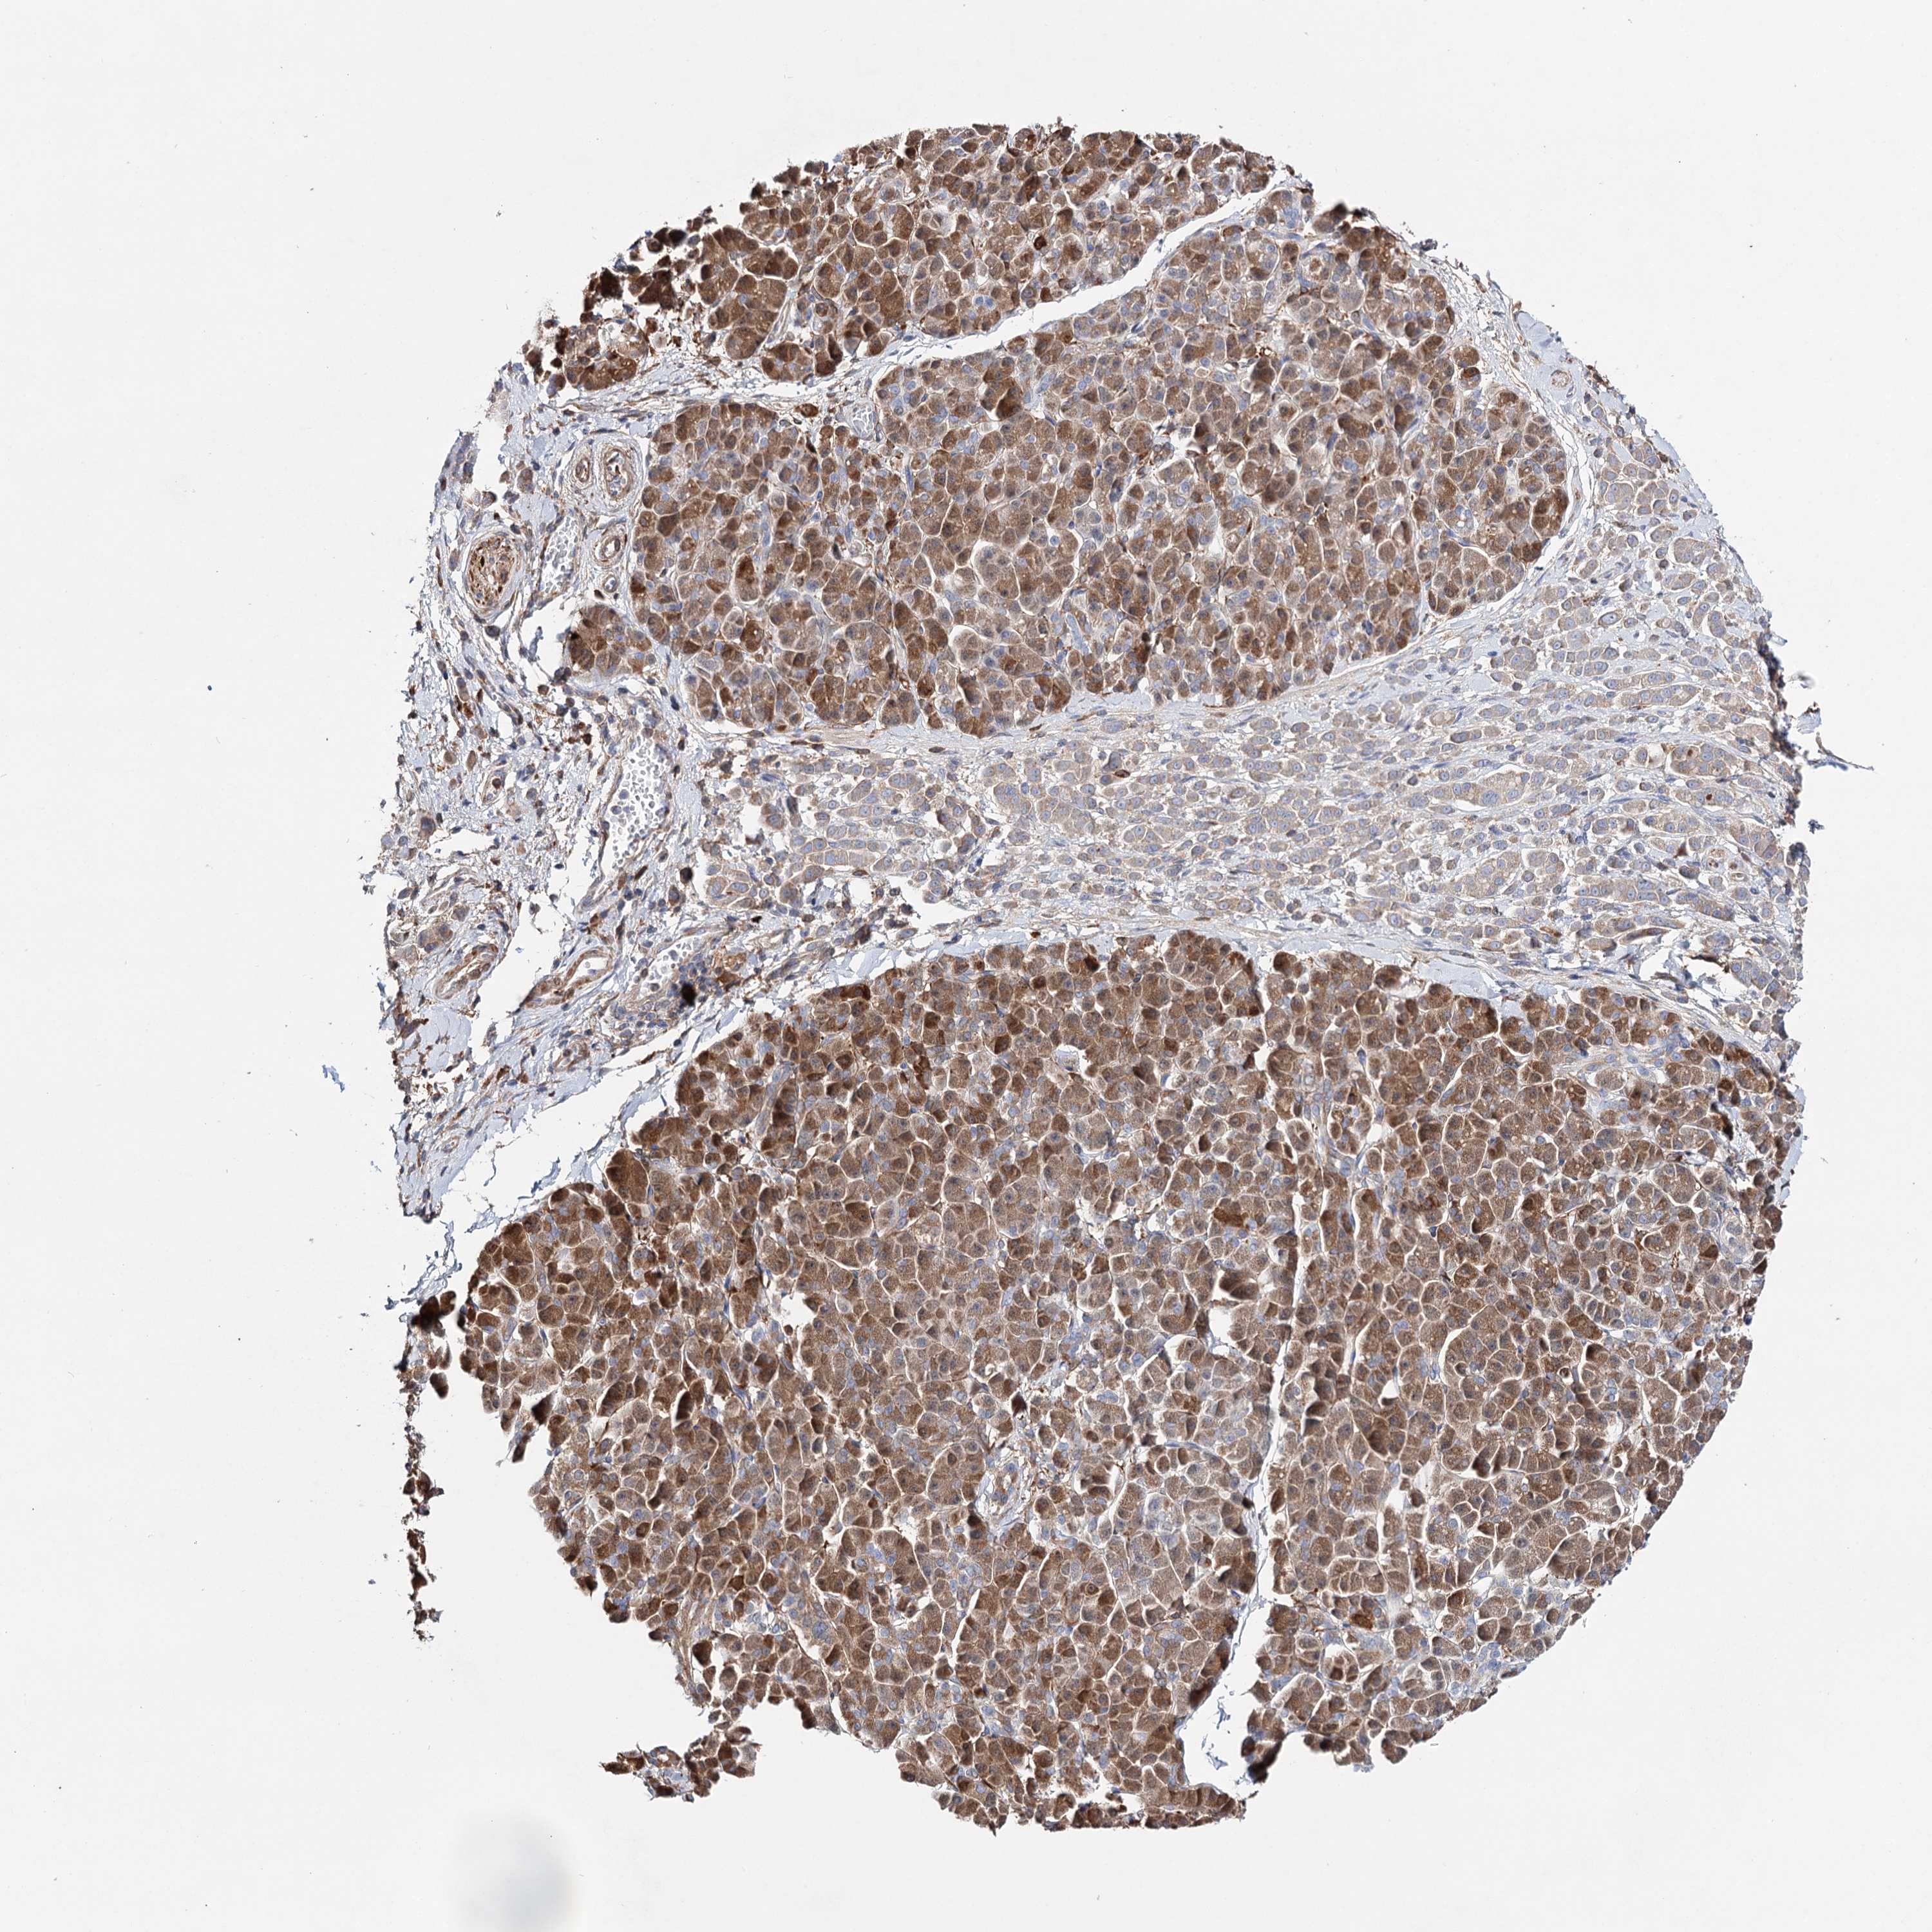

PANCREATIC CANCER - Protein expressioni

A mouse-over function shows sample information and annotation data. Click on an image to view it in a full screen mode. Samples can be filtered based on level of antibody staining by selecting one or several of the following categories: high, medium, low and not detected. The assay and annotation is described here.

Note that samples used for immunohistochemistry by the Human Protein Atlas do not correspond to samples in the TCGA dataset.

Antibody stainingi

Antibody staining in the annotated cell types in the current human tissue is reported as not detected, low, medium, or high, based on conventional immunohistochemistry profiling in selected tissues. This score is based on the combination of the staining intensity and fraction of stained cells.

Each image is clickable and will lead to virtual microscopy that enables deeper exploration of all samples and also displays staining intensity scores, fraction scores and subcellular localization as well as patient and tissue information for each sample.

Antibody HPA037786

Antibody HPA038034

Antibody HPA038867

Antibody HPA038868

Staining

Adenocarcinoma, NOS